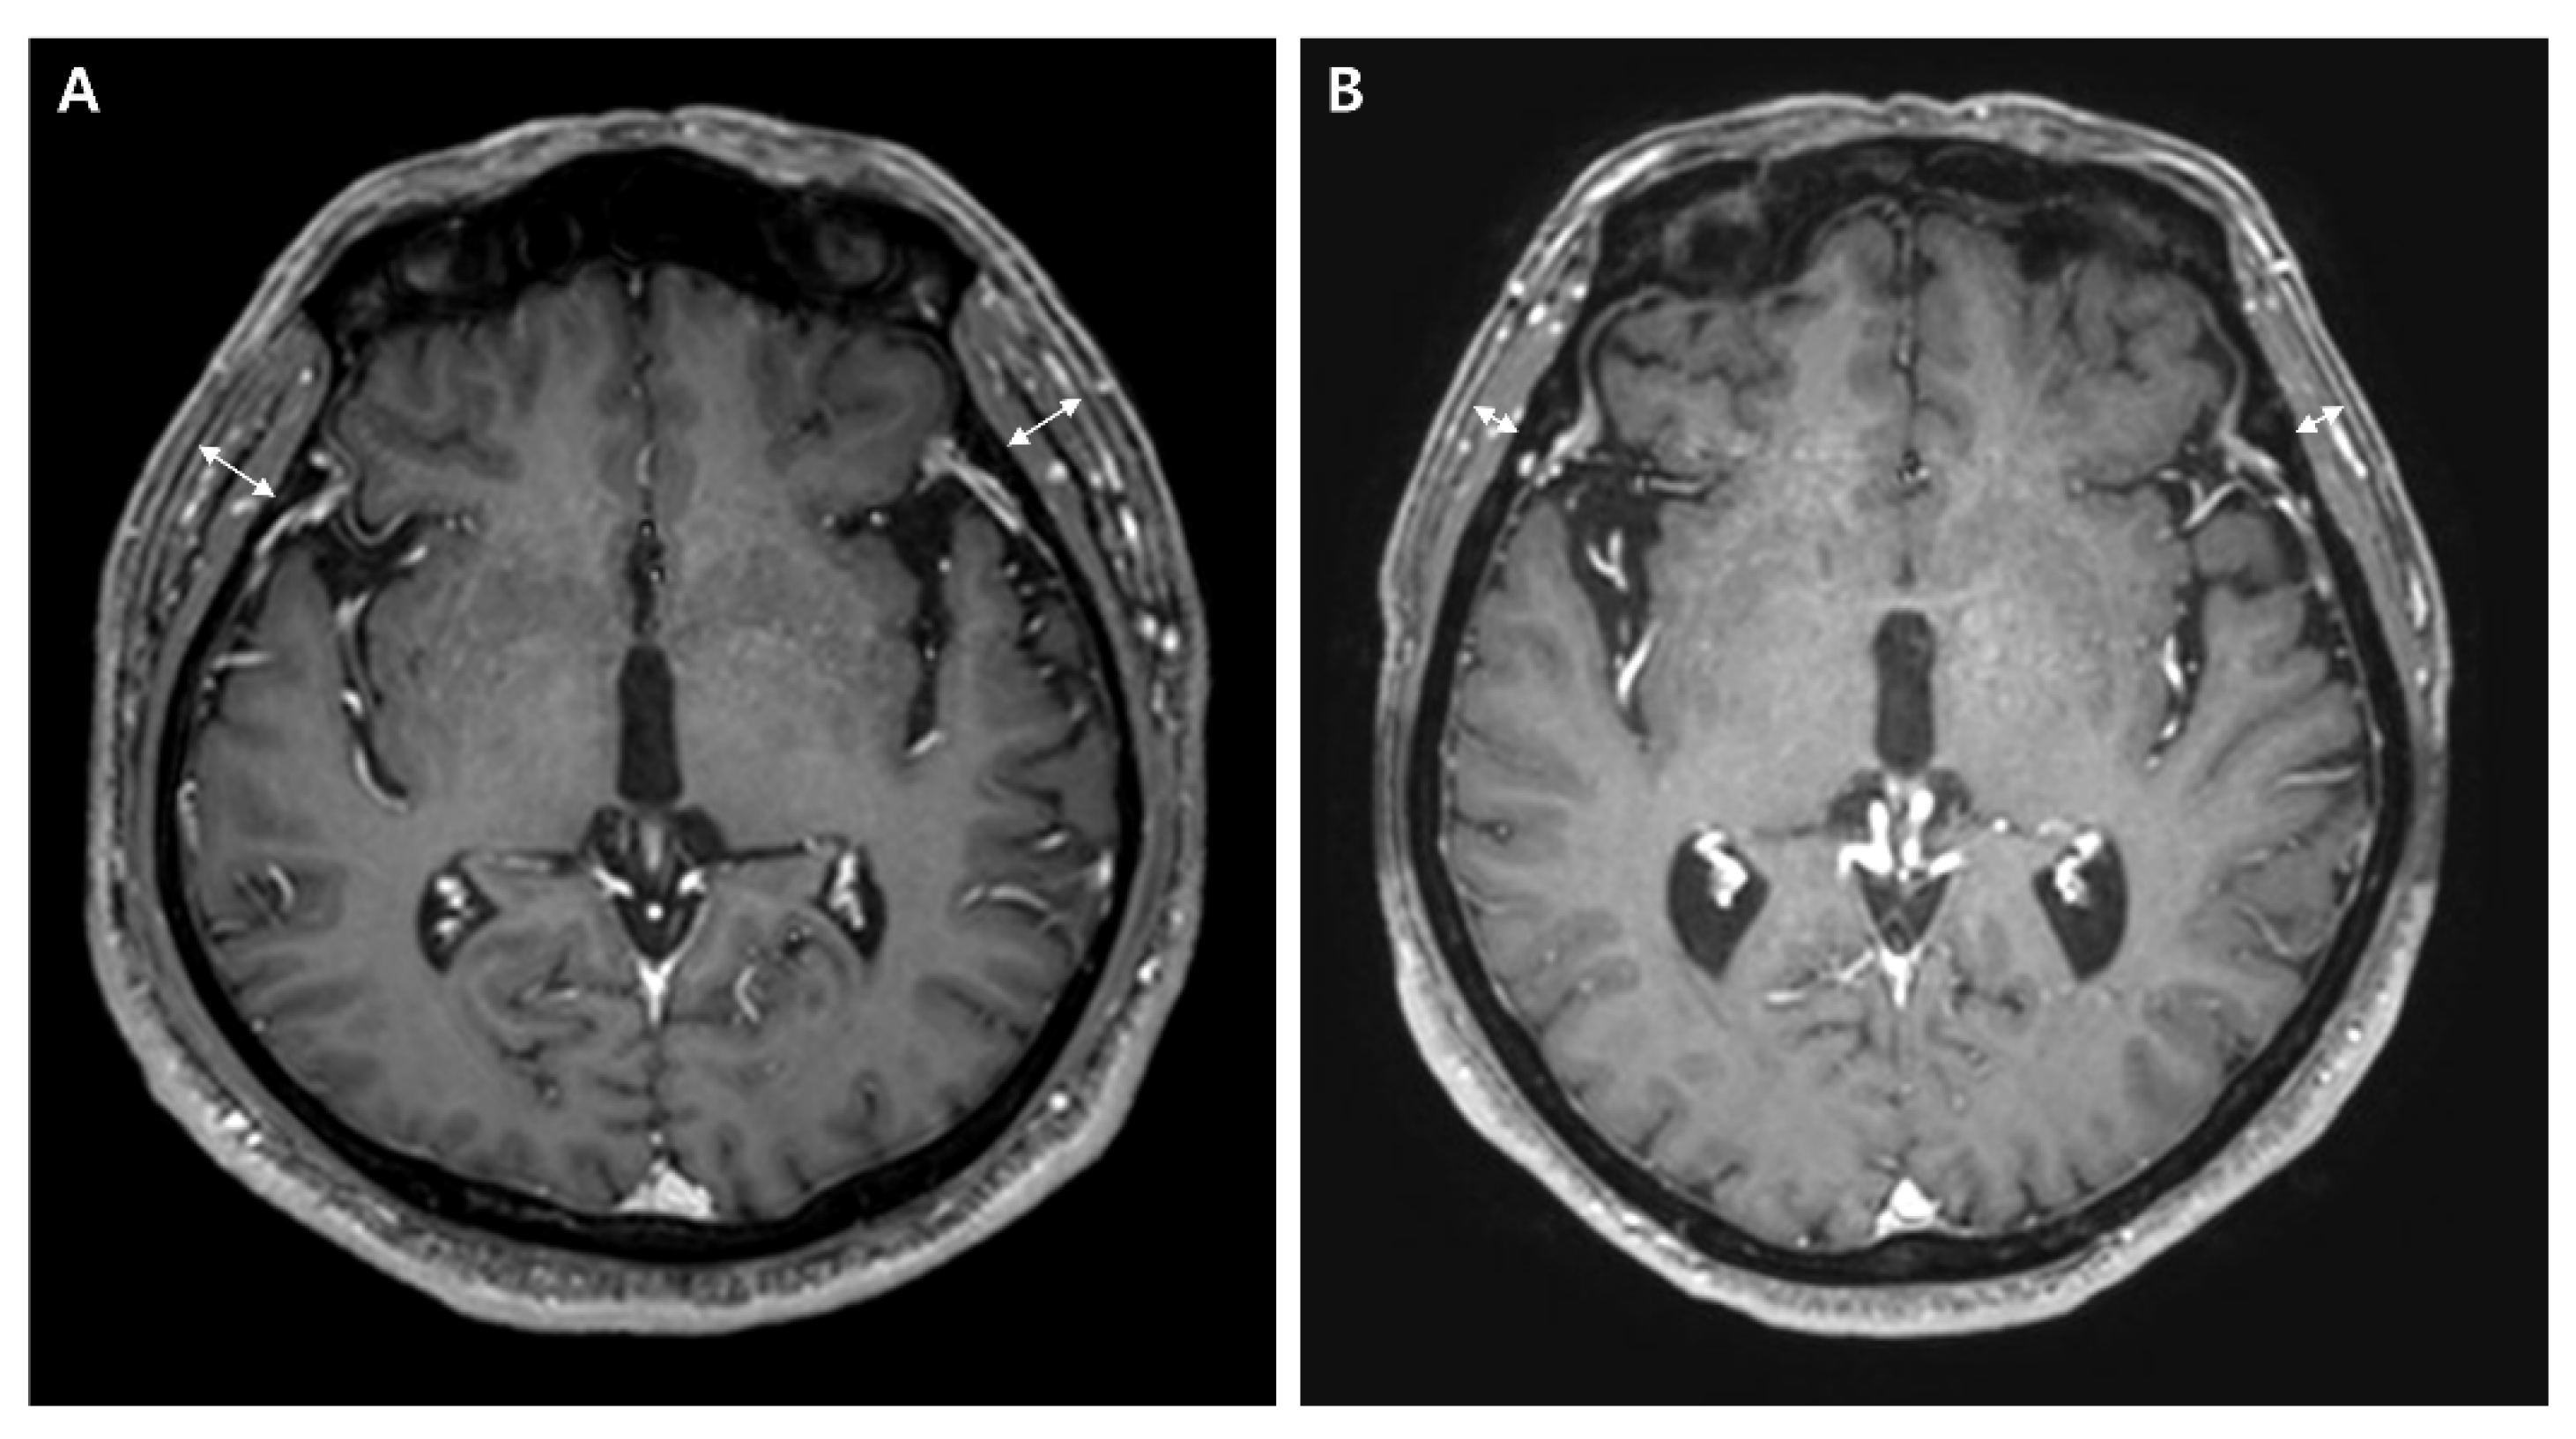

2.2. Temporal Muscle Thickness